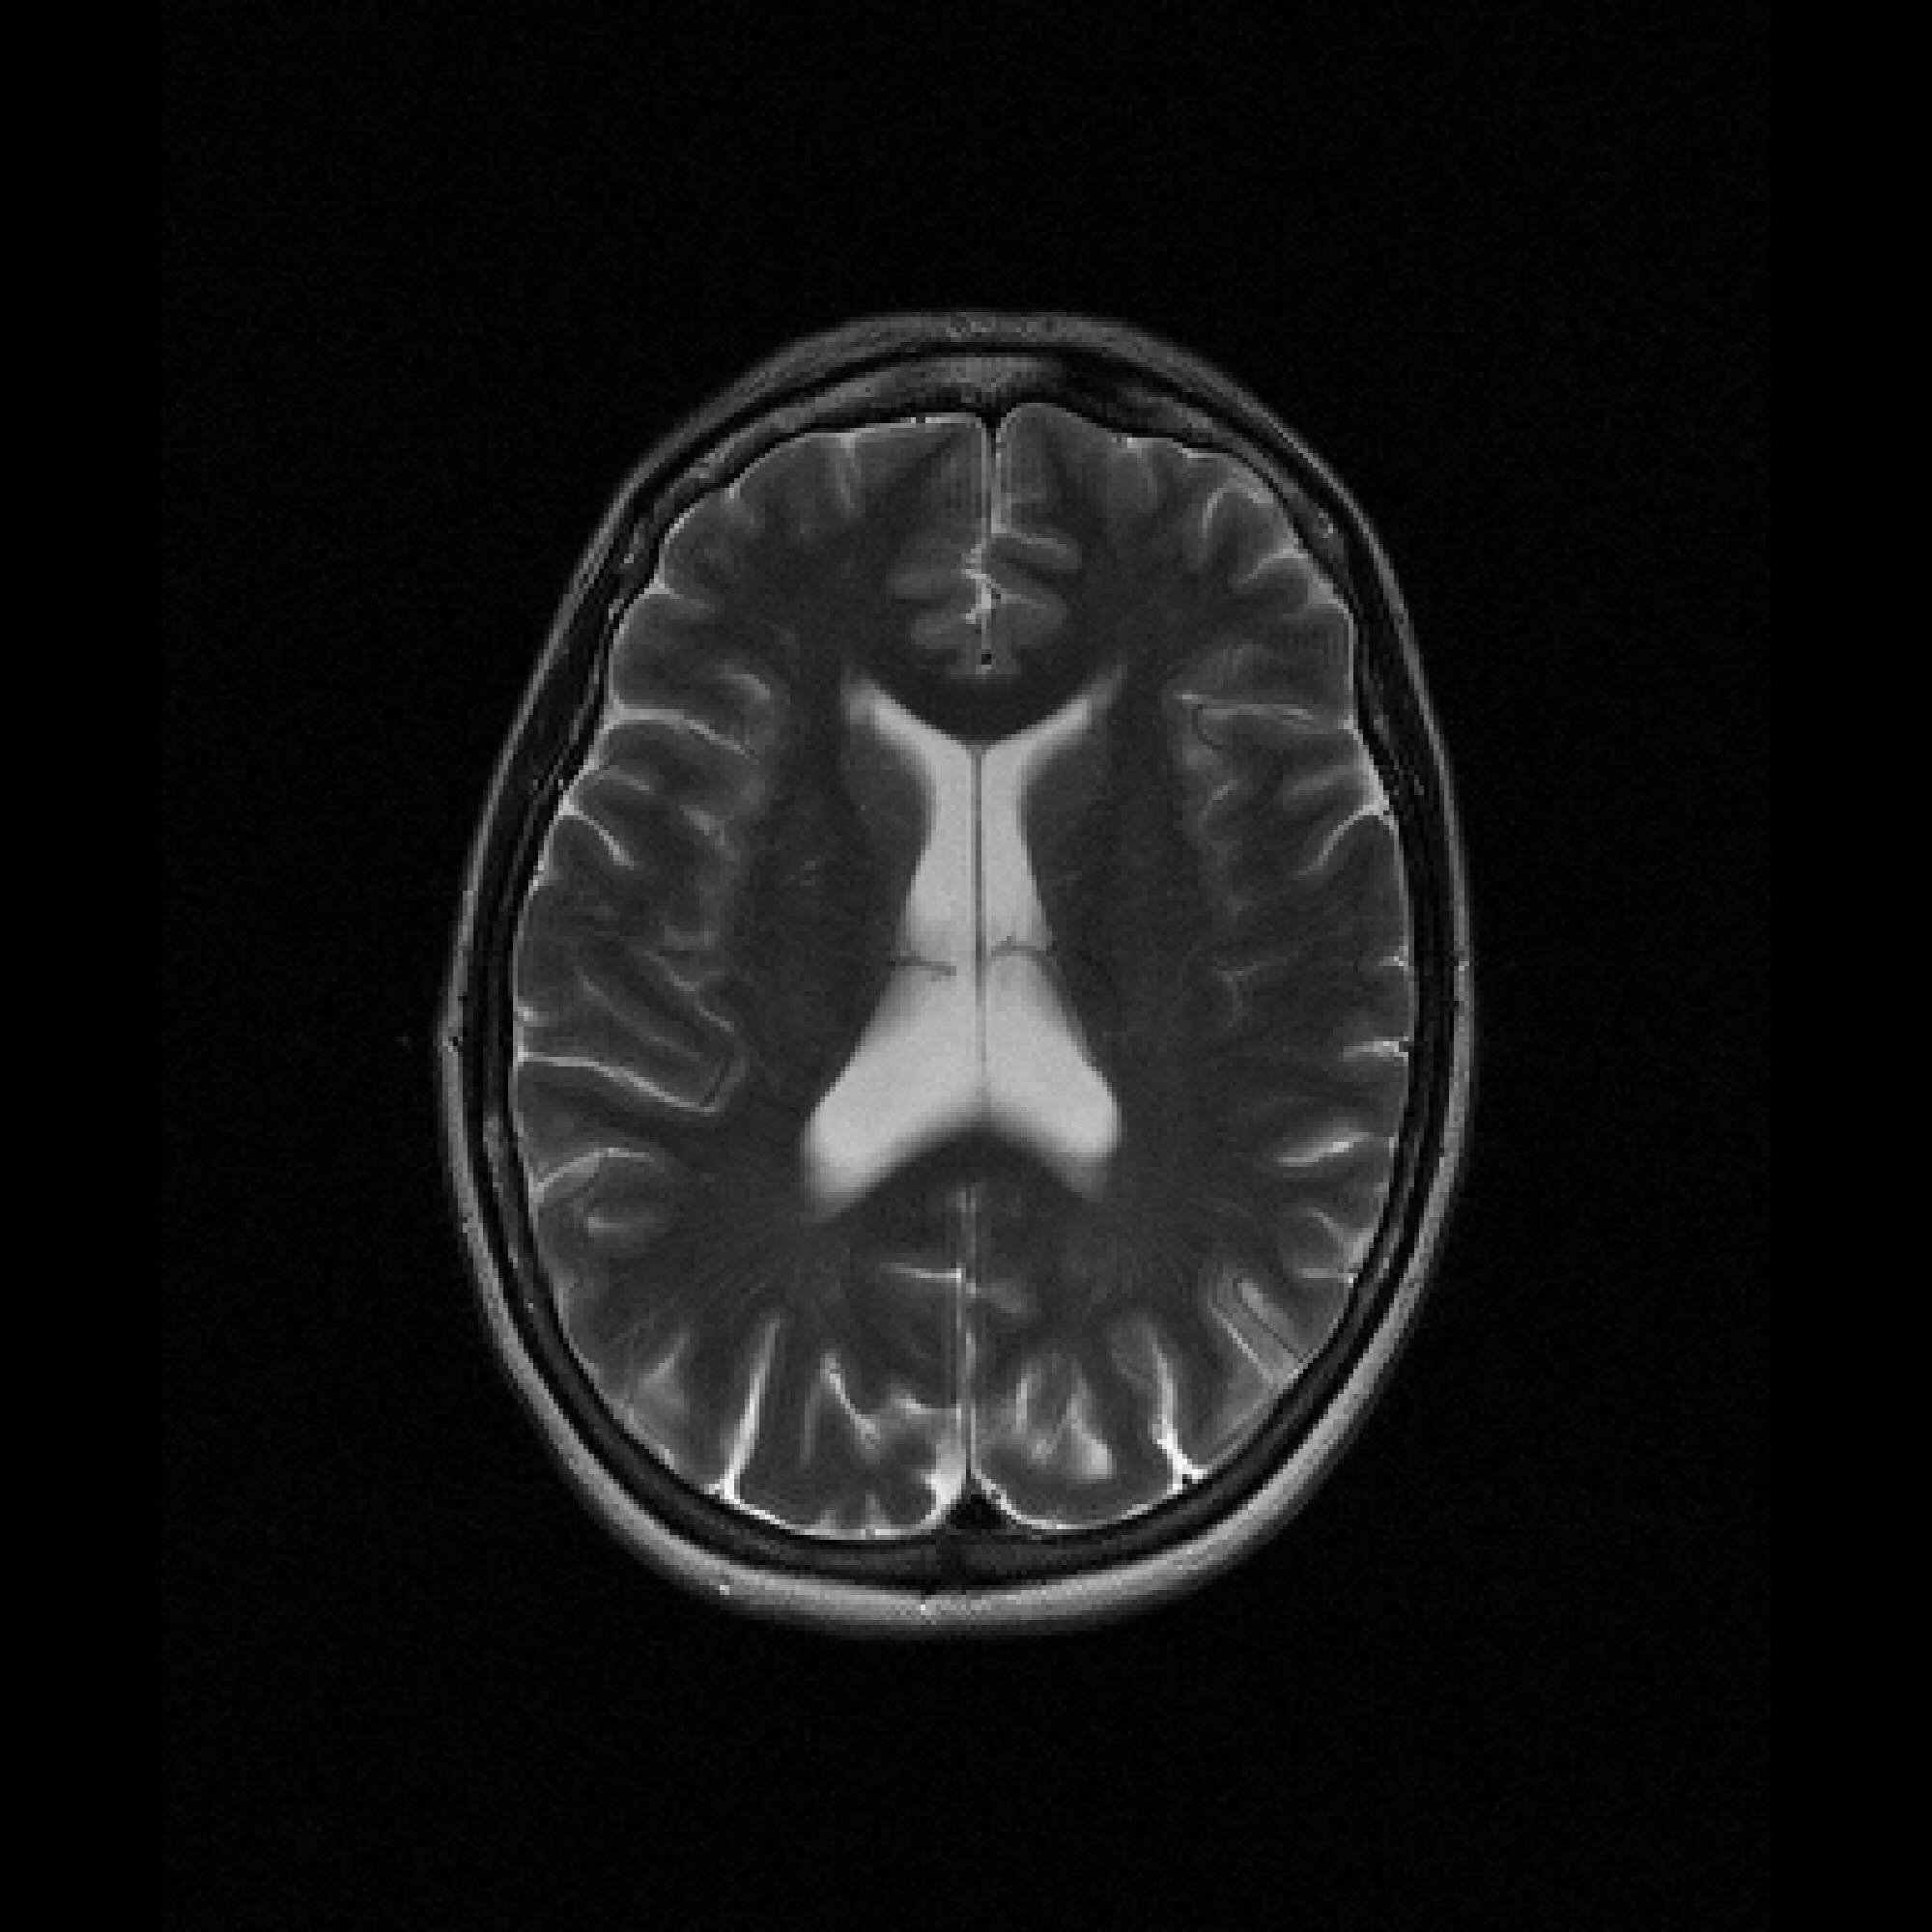

Refer to caption

Figure 2: Example MRI magnitude reconstructions with S=25S=25 training slices at acceleration (undersampling) factor R=7R=7. PaDIS-MRI reconstructions are sharper and more faithful to the fully-sampled ground truth. Insets are shown to the right to highlight detail.

Figure 2 provides a visual comparison of the reconstruction quality of each method on example slices. In reconstructions from the S=25,R=7S=25,R=7 models, FastMRI-EDM exhibits slightly more blurring and loss of fine structural details, particularly in regions with complex anatomical features. PaDIS-MRI, in contrast, preserves sharper boundaries and finer details. This enhanced data efficiency can be attributed to the patch-based prior’s ability to learn localized structural motifs more effectively from limited examples. Figure 6 in the Appendix shows similar reconstructions at S=200,R=7S=200,R=7 where FastMRI-EDM more closely approaches the performance of PaDIS-MRI but still struggles with highly detailed anatomy.